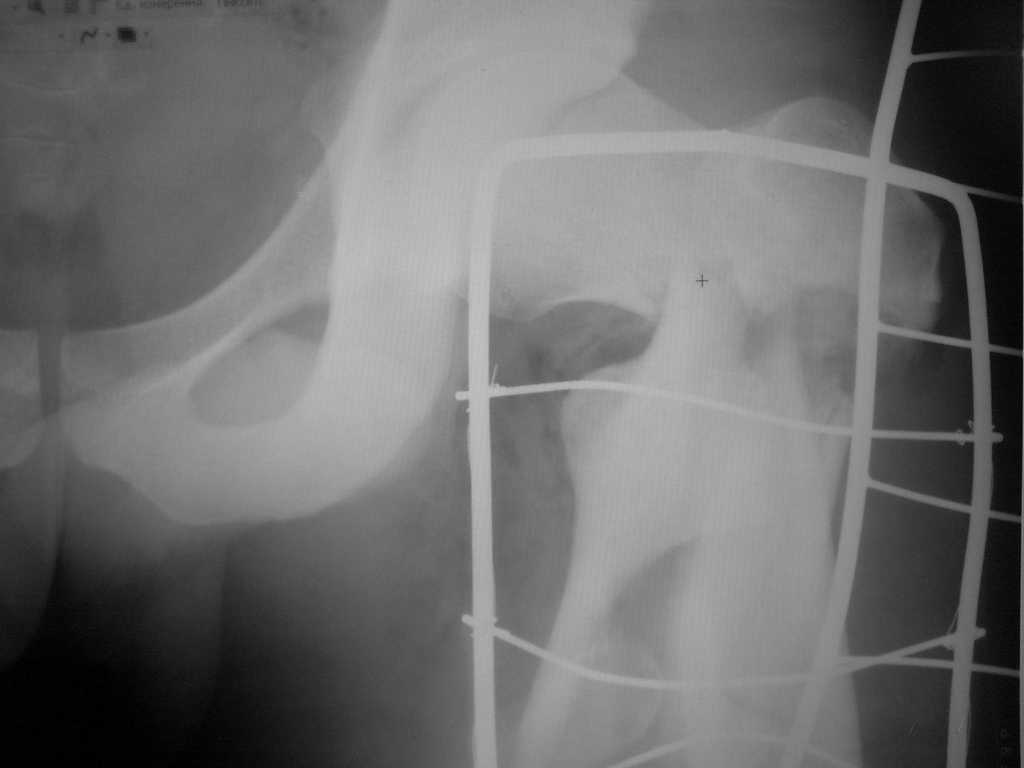

Не солидно экономить на пленке, это не делает чести презентации. Такие ограниченные нестандартные снимки приводят к тактическим ошибкам.

Предугадать распространение линий перелома при чрезвертельных и оскольчатых переломах трудно, поэтому для принятия правильного решения рекомендуется Компьютерно Томографические исследование.

При отсутствии КТ, снимок на вытяжении поможет увидеть общую картину расположения отломков, особенно потенциальные места введения импланта. Риск раскола в этом случае огромный, поэтому больной должен быть дообследован.

А так для лечения оскольчатых переломов подходят все методы, включая интра- и экстрамедуллярные в зависимости от опыта и наличия импланта.